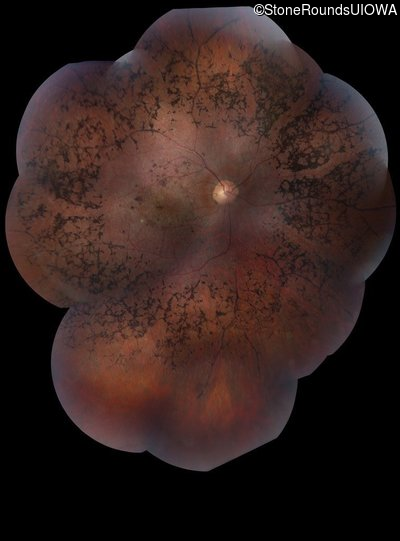

Fundus Photography - Right - 20/200 sc

Exemplar